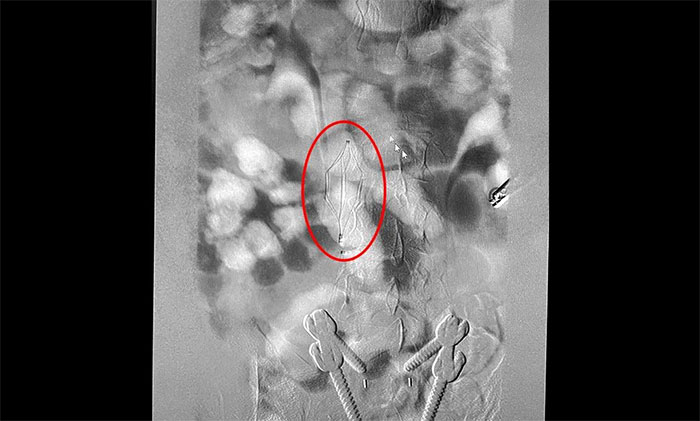

12月15日,席刚明教授在王贵平博士及介入团队协助下顺利行将一个形似伞状的人工滤器经患者右侧股静脉穿刺迅速置入肾静脉下方,“网”住了通往心血管和肺部的致命栓子,阻挡血液栓子进入肺动脉,及时挽救了患者生命。之后对病变血管进行了血栓抽吸术,及接触性溶栓,抽出了大量血栓,复查下肢造影示血栓基本消失,下肢静脉血管再通,整个手术顺利完成。术后,患者下肢肿胀好转。

▲ 下腔静脉滤器顺利置入

下腔静脉滤器置入是为了预防下腔静脉系统栓子脱落引起肺栓塞而设计的一种装置,分为永久性和可回收两种。可回收滤器可经健侧股静脉、亦可经颈内静脉置入。该手术通过滤器输送器,将滤器在X线透视下送入,确定位置无误后,后撤输送器直至滤器弹开、释放。

下腔静脉滤器置入术创伤小,可回收性好,既能截获栓子,又能保持下腔静脉的通畅不影响静脉回流。有效防止了肺栓塞的发生,并大大的降低了并发症的发生,被誉为“生命的保护伞”,为长期卧床患者因深静脉血栓导致的肺栓塞带来新的解决方案。置入下腔静脉滤器可使肺栓塞发生率从60%-70%下降为0.9%-5%,该项技术为下一步手术取栓、药物溶栓提供了强有力的支持,使深静脉血栓得到更有效的治疗。